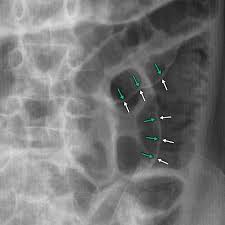

Rigler Sign

See the outline of the small and large bowel outlines - outlined by intraperitonial gas

Free air - Best seen in the right upper quadrant